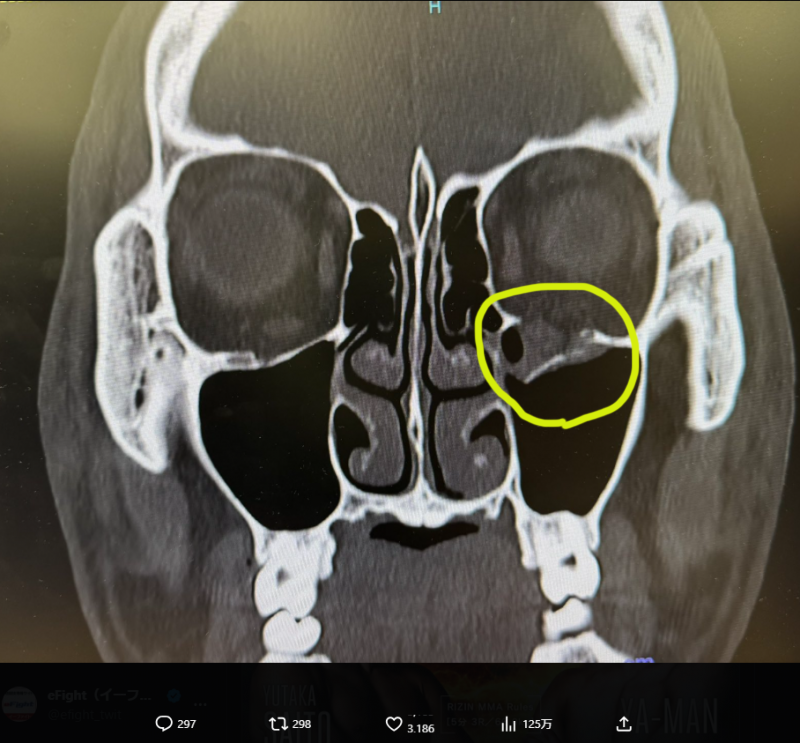

YA-MANが公開したレントゲン。左目の下の骨がポッキリ折れている(@yaman_kosf)